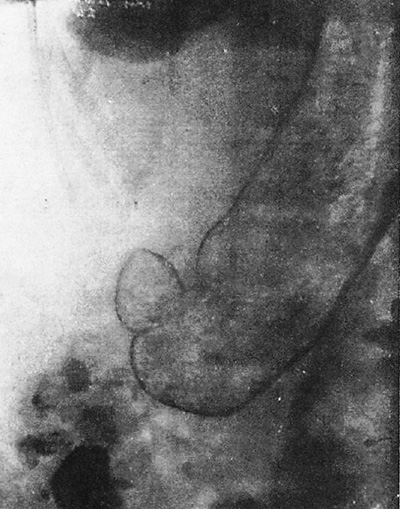

図7. 小さな大腸ポリープの二重造影像.

【要旨・解説】1923年にFischerが大腸二重造影の基礎を作ったが,その画質は限られたもので小病変の診断は難しかった.1950年代,大腸癌と腺腫の関係が知られるようになり,癌の予防策として小さなポリープの発見が重要と考えられるようになった.スウェーデンのWelinは,これを目指して,それまで知られていた大腸造影法を組合わせて新たな方法を開発した.著者が最も強調しているのは徹底した前処置の必要性で,このために前夜を含めて計3回の洗腸を行ない,緩下剤や粘膜分泌抑制剤も併用している.造影に際しては,まずバリウムを横行結腸の中ほどまで充盈していったんこれを排出する.その後あらためて少量の高濃度バリウムを注入し,空気を送入して全結腸の粘膜二重造影像を得る.充盈したバリウムをいったん排出するという二度手間がかかる点はFischer法と同様であるが,低濃度バリウムを大量に使用するFischer法に対して,高濃度バリウムを少量使用して二重造影を行なう点が大きな違いである.これに撮影条件(小焦点管球,遠距離撮影,高圧撮影)の改良も加わって,供覧されている写真を見る限り,現在の注腸造影の画質にかなり近づいたものとなっており,径数mmのポリープも良好に描出できるとしている(図7).ただ,ここで主に扱われているのは直腸~S状結腸のポリープで,右側結腸についてどの程度診断できたのかは不明である.

本法を開発したWelinは,1923年に筆頭著者としてその概要を発表しているが[15],本稿はその直後に第2報として,実際に検査を行なった助手のAndrénを筆頭著者として技術的詳細についてより詳しく述べたものである.Fischer法とWelin法の実際については,本稿の著者Andrénに直接取材した仁羽の総説に詳しい[16].